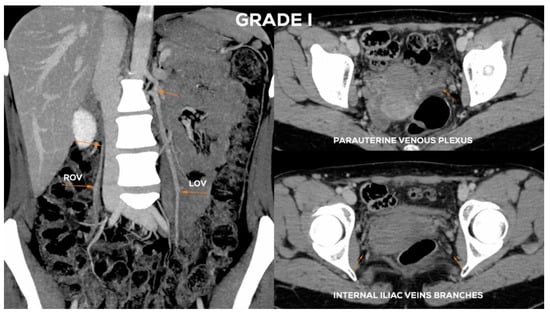

4.2.1. Grade I (GI)

| GI | <6 | (−/+) | <5 | <5 | <5 | (−) | <5 | <5 |